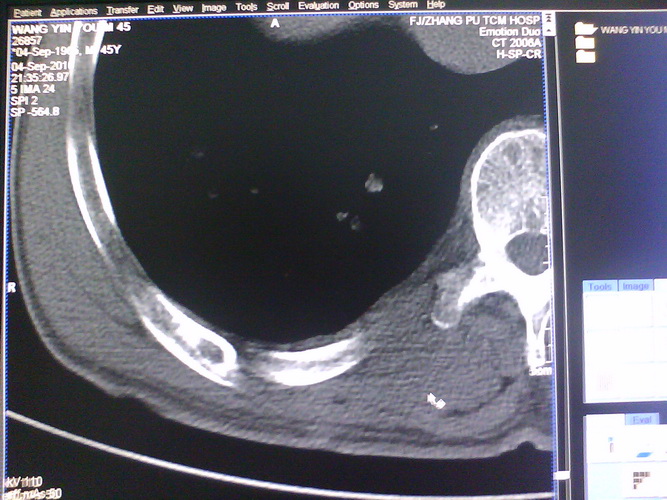

患者,男性,41y,外伤病号,来拍片,发现右侧第9后肋,肋骨膨大,有密度不均,想问大家,是否有问题,要考虑什么东西,谢谢

右侧第九后肋骨纤维结构不良。

考虑骨纤维异常增殖症(混合型)。